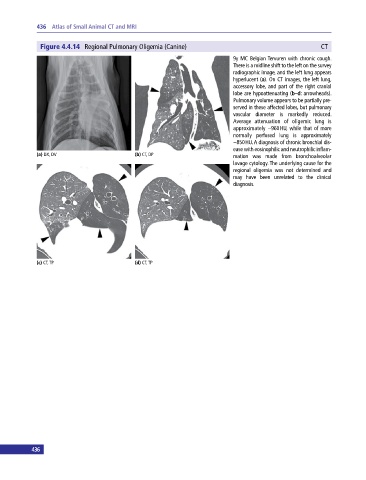

Figure 4.4.14 Regional Pulmonary Oligemia (Canine) CT

9y MC Belgian Tervuren with chronic cough.

There is a midline shift to the left on the survey

radiographic image, and the left lung appears

hyperlucent (a). On CT images, the left lung,

accessory lobe, and part of the right cranial

lobe are hypoattenuating (b–d: arrowheads).

Pulmonary volume appears to be partially pre-

served in these affected lobes, but pulmonary

vascular diameter is markedly reduced.

Average attenuation of oligemic lung is

approximately −960 HU, while that of more

normally perfused lung is approximately

−850 HU. A diagnosis of chronic bronchial dis-

ease with eosinophilic and neutrophilic inflam-

(a) DX, DV (b) CT, DP mation was made from bronchoalveolar

lavage cytology. The underlying cause for the

regional oligemia was not determined and

may have been unrelated to the clinical

diagnosis.